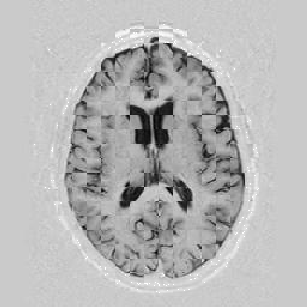

Another larger group of experiments enabled me to study the effects of multi-scale NRR. The results are shown in the form of chequerboard images in Figure [*]. In terms of resolution levels, higher numbers mean that the images are coarser.

Figure: Multi-scale NRR (increasing resolution). From left to right, top then bottom:before NRR; after 5 iterations of NRR at level 2 (higher is coarser); after another 5 iterations of NRR at level 1.